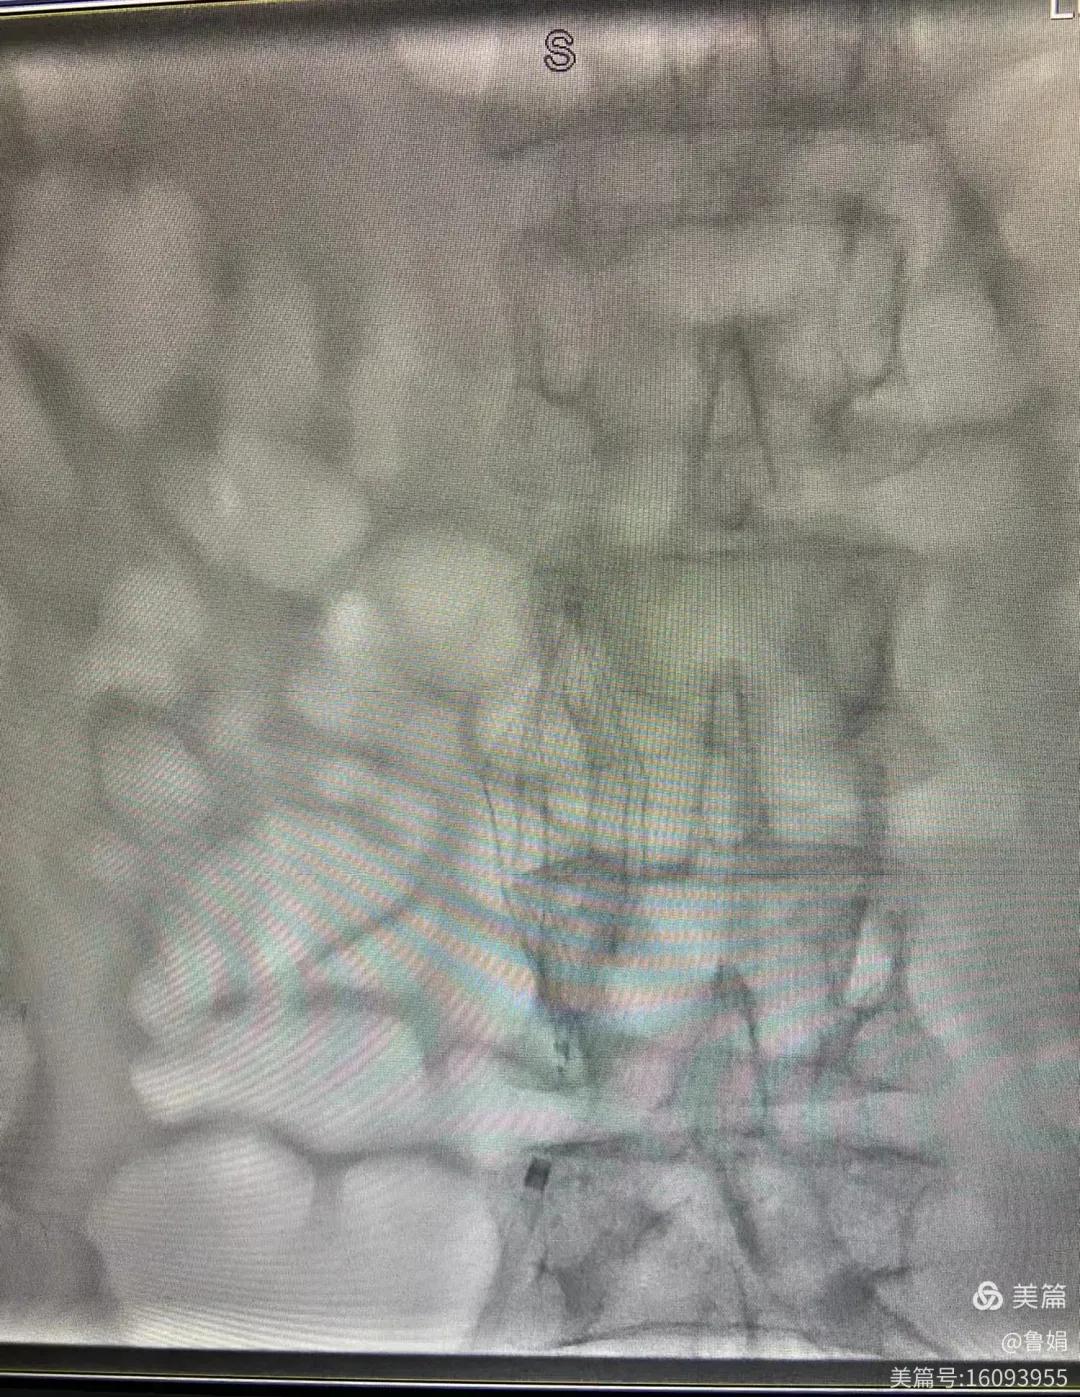

圖片術(shù)后濾器順利植入

經(jīng)認真查看患者病例,探討患者病情及術(shù)中潛在風(fēng)險因素,多科會診后急診為患者開展介入手術(shù),術(shù)中周創(chuàng)業(yè)副主任、孫亞中副主任中醫(yī)師二人通力合作,手術(shù)順利,病人術(shù)中出血少,生命體征平穩(wěn),現(xiàn)在腦二科病房繼續(xù)對癥治療。(介入中心:魯娟)